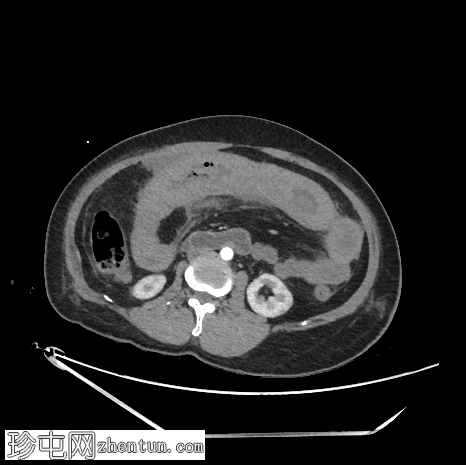

轴位

非增强

肠壁强化减弱,高度提示肠缺血。

腹腔内可见中等量腹水。

低灌注综合征:

血管表现

腹主动脉管径变细:前后径12 mm

腹主动脉分支变细:腹腔干5.3 mm;肝总动脉3.2 mm;脾动脉1.5 mm;肠系膜动脉直径 4.4 mm

下腔静脉扁平征

内脏表现

脾脏灌注不足,脾脏体积略有缩小:初始测量值为 57 x 35 x 38 mm,后续影像学检查缩小至 56 x 31 x 33 mm

肝脏灌注不足:肝实质呈不均匀强化,主要累及右肝叶

双侧肾上腺强化

双侧可见肾图增高、延长且呈条纹状

影像学表现提示自发性空肠壁内出血,伴有肠壁缺血的证据,导致出血性休克和弥漫性血管痉挛。CT 扫描期间,患者正在接受血管加压药物支持。

红细胞计数:1,77。血红蛋白:54 克/升。红细胞压积:16.4%。

国际标准化比值:28.3。